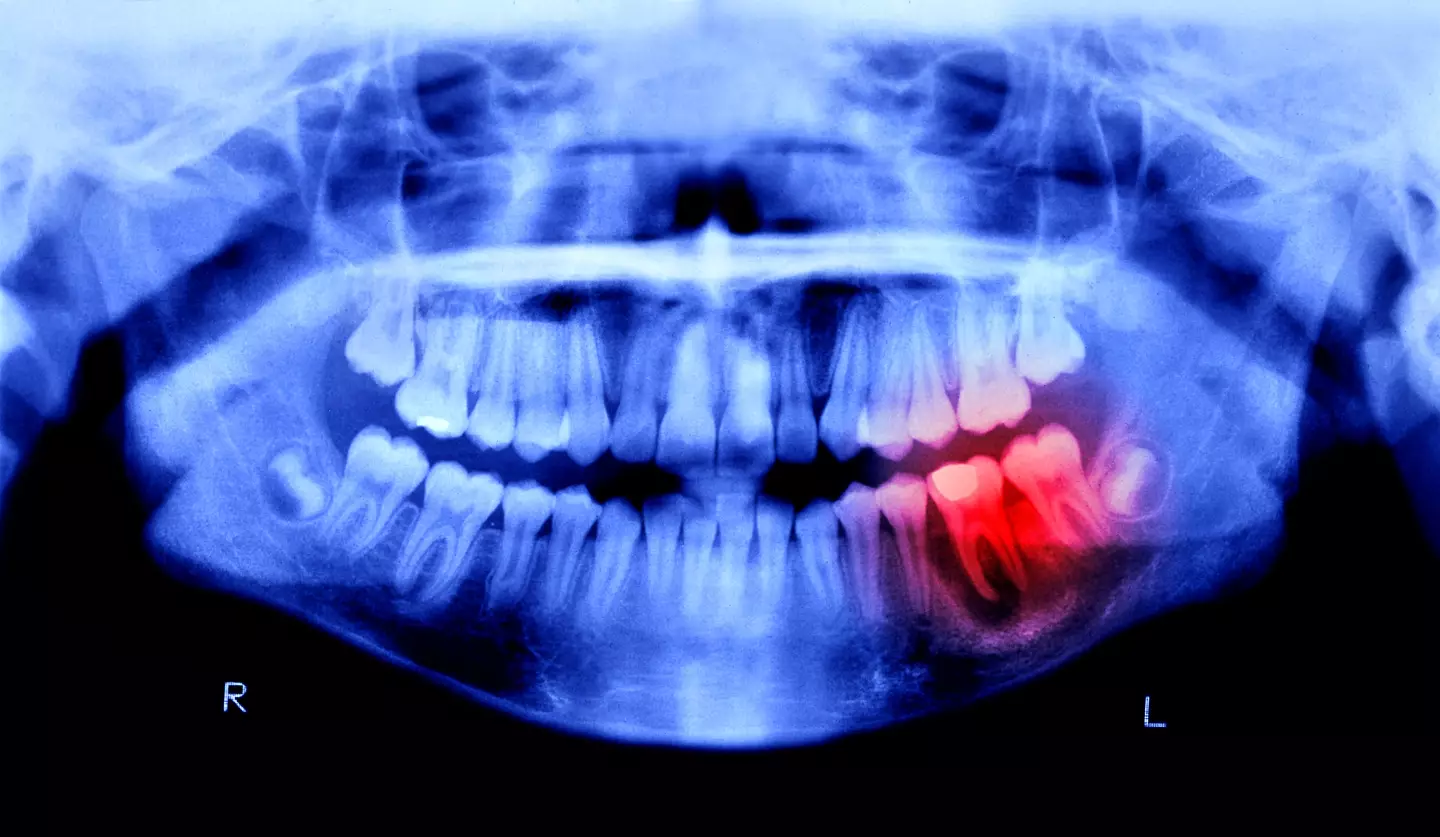

He recommended that you stick to a strict brushing regime, and made sure you got into the gaps between your teeth, and the ones between your teeth and gums.

According to the NHS, symptoms of gum disease include:

- Bleeding gums when you brush your teeth, floss or eat hard foods.

- Your gums becoming swollen, red and sore.

- Bad breath and a bad taste in the mouth.

- Your gums shrinking.

- Your teeth becoming loose or falling out.

If you're experiencing these symptoms then you should go and see your dentist, while there are times when you need to book an urgent appointment.

Very sore and swollen gums are a major warning sign, while your teeth getting loose or falling out is a clear sign that you need to get to a dentist ASAP.